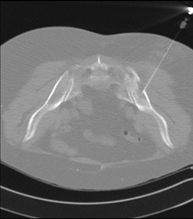

Prova que consisteix en obtenir una mostra de teixit de lesions toràciques, com per exemple masses pulmonars, mediastíniques, lesions òssies, etc. Per això s'administra anestèsia local sobre la zona de punció, que es realitza amb agulles de calibre fi. Tot el procediment es realitza controlat amb imatges obtingudes per tomografia computaritzada (TC) en diversos moments de la punció, mitjançant un equip de Fluoroscòpia-TC. Després de la prova, el pacient resta unes hores hospitalitzat. És necessari portar proves de coagulació abans de la punció. - CT-guided thoracic biopsy

It consists of obtaining a tissue sample from a specific thoracic lesion, such as the lung, mediastinum, sternum, etc. It is sometimes performed under sedation with the help of an anaesthesia team. Needles are used to draw a cylinder sample from the lesion to be studied, which is then sent to the Pathology Department for histological analysis. The entire procedure is performed with guidance from images obtained by computed tomography (CT) at various stages of the biopsy, using fluoroscopy-CT equipment. After the test, the patient remains in hospital under observation. Coagulation tests must be performed before the puncture.